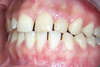

Notre patiente ne sourit pas à cause de sa dent naine à droite et de ses espaces interdentaires.

Avant l'opération

En 2 séances, elle resplendit grâce à la pose de facettes collées.